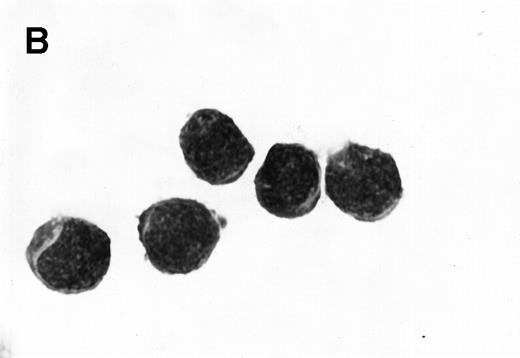

Morphology of sorted CD34+ cells obtained from MPB. The regions R3 (CD38−/low in A), R4 (CD382+ in B), and R5 (CD383+ in C) were stained with Wright Giemsa’s stain, visualized by light microscopy, and photographed at 1,000× magnification. Data show one representative experiment of six.

Because we obtained two populations of bcl-2 within the CD34s+ cells, we were interested in examining the morphology of these cells. We went on to sort CD34s+ cells from the three gates (CD38−/low, CD382+, and CD383+). Morphological examination of cytospins prepared from R3, R4, and R5 showed progressively larger cells with distinct morphologies (Fig 3). Among the CD34+/CD38−/low cells, 87% to 91% were lymphoid-like with scanty cytoplasm, large homogeneous nuclei, and rare nucleoli (Fig 3A). The contaminating cells were mainly lymphocytes (3% to 5%) and mature myeloid cells (6% to 8%). CD382+ cells were lymphoblast-like with more cytoplasm, large nuclei, and one or more nucleoli (Fig 3B). CD383+ cells were myeloblast-like with large amounts of cytoplasm containing granules, large granular nuclei, and many nucleoli (Fig 3C).